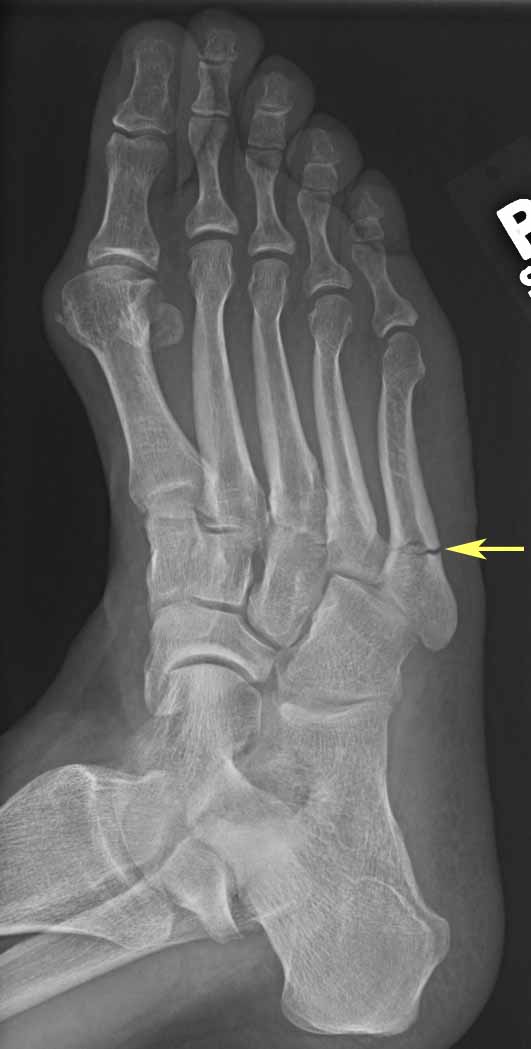

Oblique view of the foot demonstrating an Jones fracture. Download Scientific Diagram How To Wrap Foot For Jones Fracture a jones fracture is a fracture of the bone on the outside of the foot. Learn how to recognize a jones fracture s well as treatment and. Ice, elevate, and take pain medication. a jones fracture occurs when one of the bones on the top of the foot breaks. jones fractures are caused when you put sudden. How To Wrap Foot For Jones Fracture.